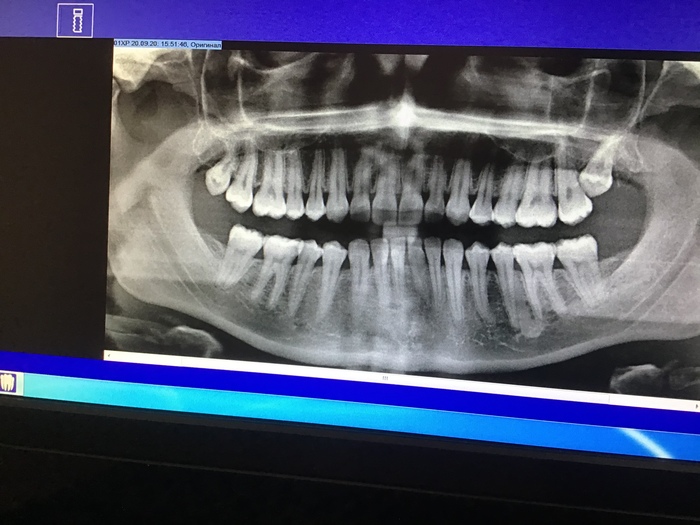

Я была у стоматолога с такой проблемой: в верхней левой части немного болят зубы при надавливании примерно в районе 4,5,6 зубов, что портит впечатление от приёмов пищи. Врач осмотрел, но никаких дефектов не увидел, в том числе под десной, так как делал чистку. Порекомендовал сделать панорамный снимок. Так как в нашем городе таких снимков не делают, через пару недель я поехала в другой город и вот он снимок. Насколько я понимаю, проблема может быть в зубе мудрости растущем хрен знает куда (прямо в корень соседнего зуба сбоку). Зуб мудрости на поверхности не виден, он глубоко под десной и десна в полном порядке.